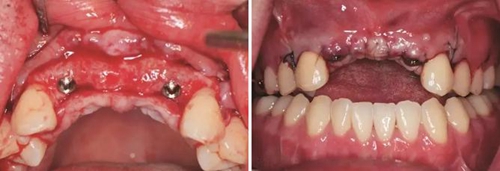

圖1 植骨術(shù)前口內(nèi)正面觀 圖2 植骨術(shù)前口內(nèi)頜面觀

圖11 植骨后6月種植術(shù)前 圖12 種植術(shù)前翻瓣后見少量鈦釘螺紋暴露

圖13 取出鈦釘后 圖14 攜帶體示植體位置方向良好

圖15 種植術(shù)后 圖16 種植后嚴(yán)密縫合創(chuàng)口

圖17 CBCT測量骨量變化 圖18 早期修復(fù)戴牙當(dāng)天